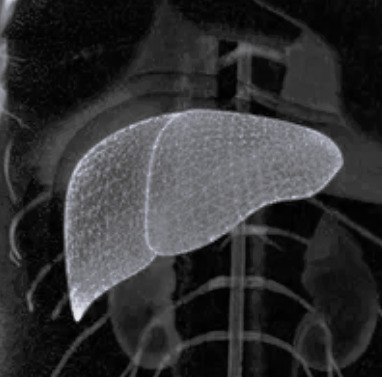

Мрт рака печени

Мрт рака печени 112 фото